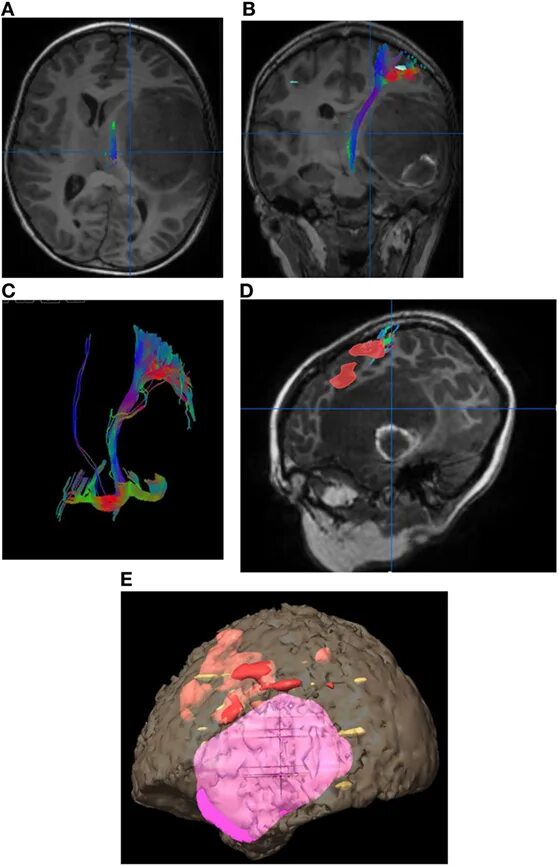

Diffusion tensor